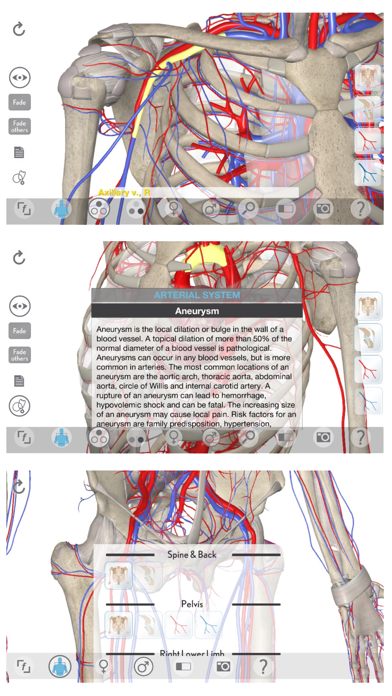

1. 3D Organon Anatomy – Heart, Arteries, and Veins is a feature-rich interactive cardiovascular atlas enhanced with quality anatomy descriptions and texts with frequently encountered clinical correlations.

4. + All featured text descriptions and clinical correlations are written by professors of anatomy and medical professionals.

6. An all-in-one solution for learning clinical, topographic and systems-based anatomy.

7. + Bonus body systems: Skeletal system, Connective system.

9. The app includes skeletal system and connective tissues as a bonus.